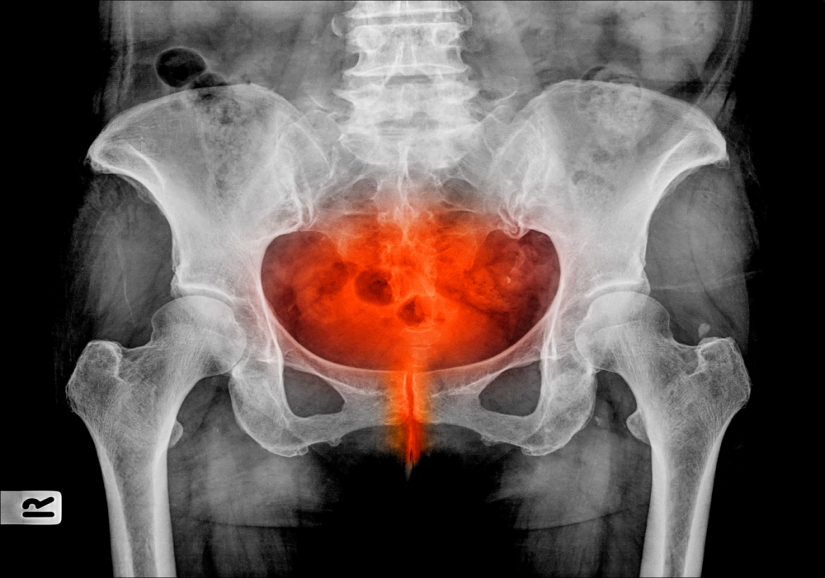

Trata-se de inflamação da bexiga urinária, muitas vezes provocada por infecção aguda do trato urinário.

A cistite ocorre muitas vezes associada a outros problemas do sistema urinário, como doenças venéreas, cálculos, pielonefrite, hipertrofia de próstata e uretrite (inflamação da uretra).

Considerando-se a continuidade anatômica do sistema urinário e a semelhança entre os sintomas de infecção dos seus vários componentes, alguns estudiosos chamam de “síndrome uretral aguda” diversas perturbações urinárias de fundo infeccioso.